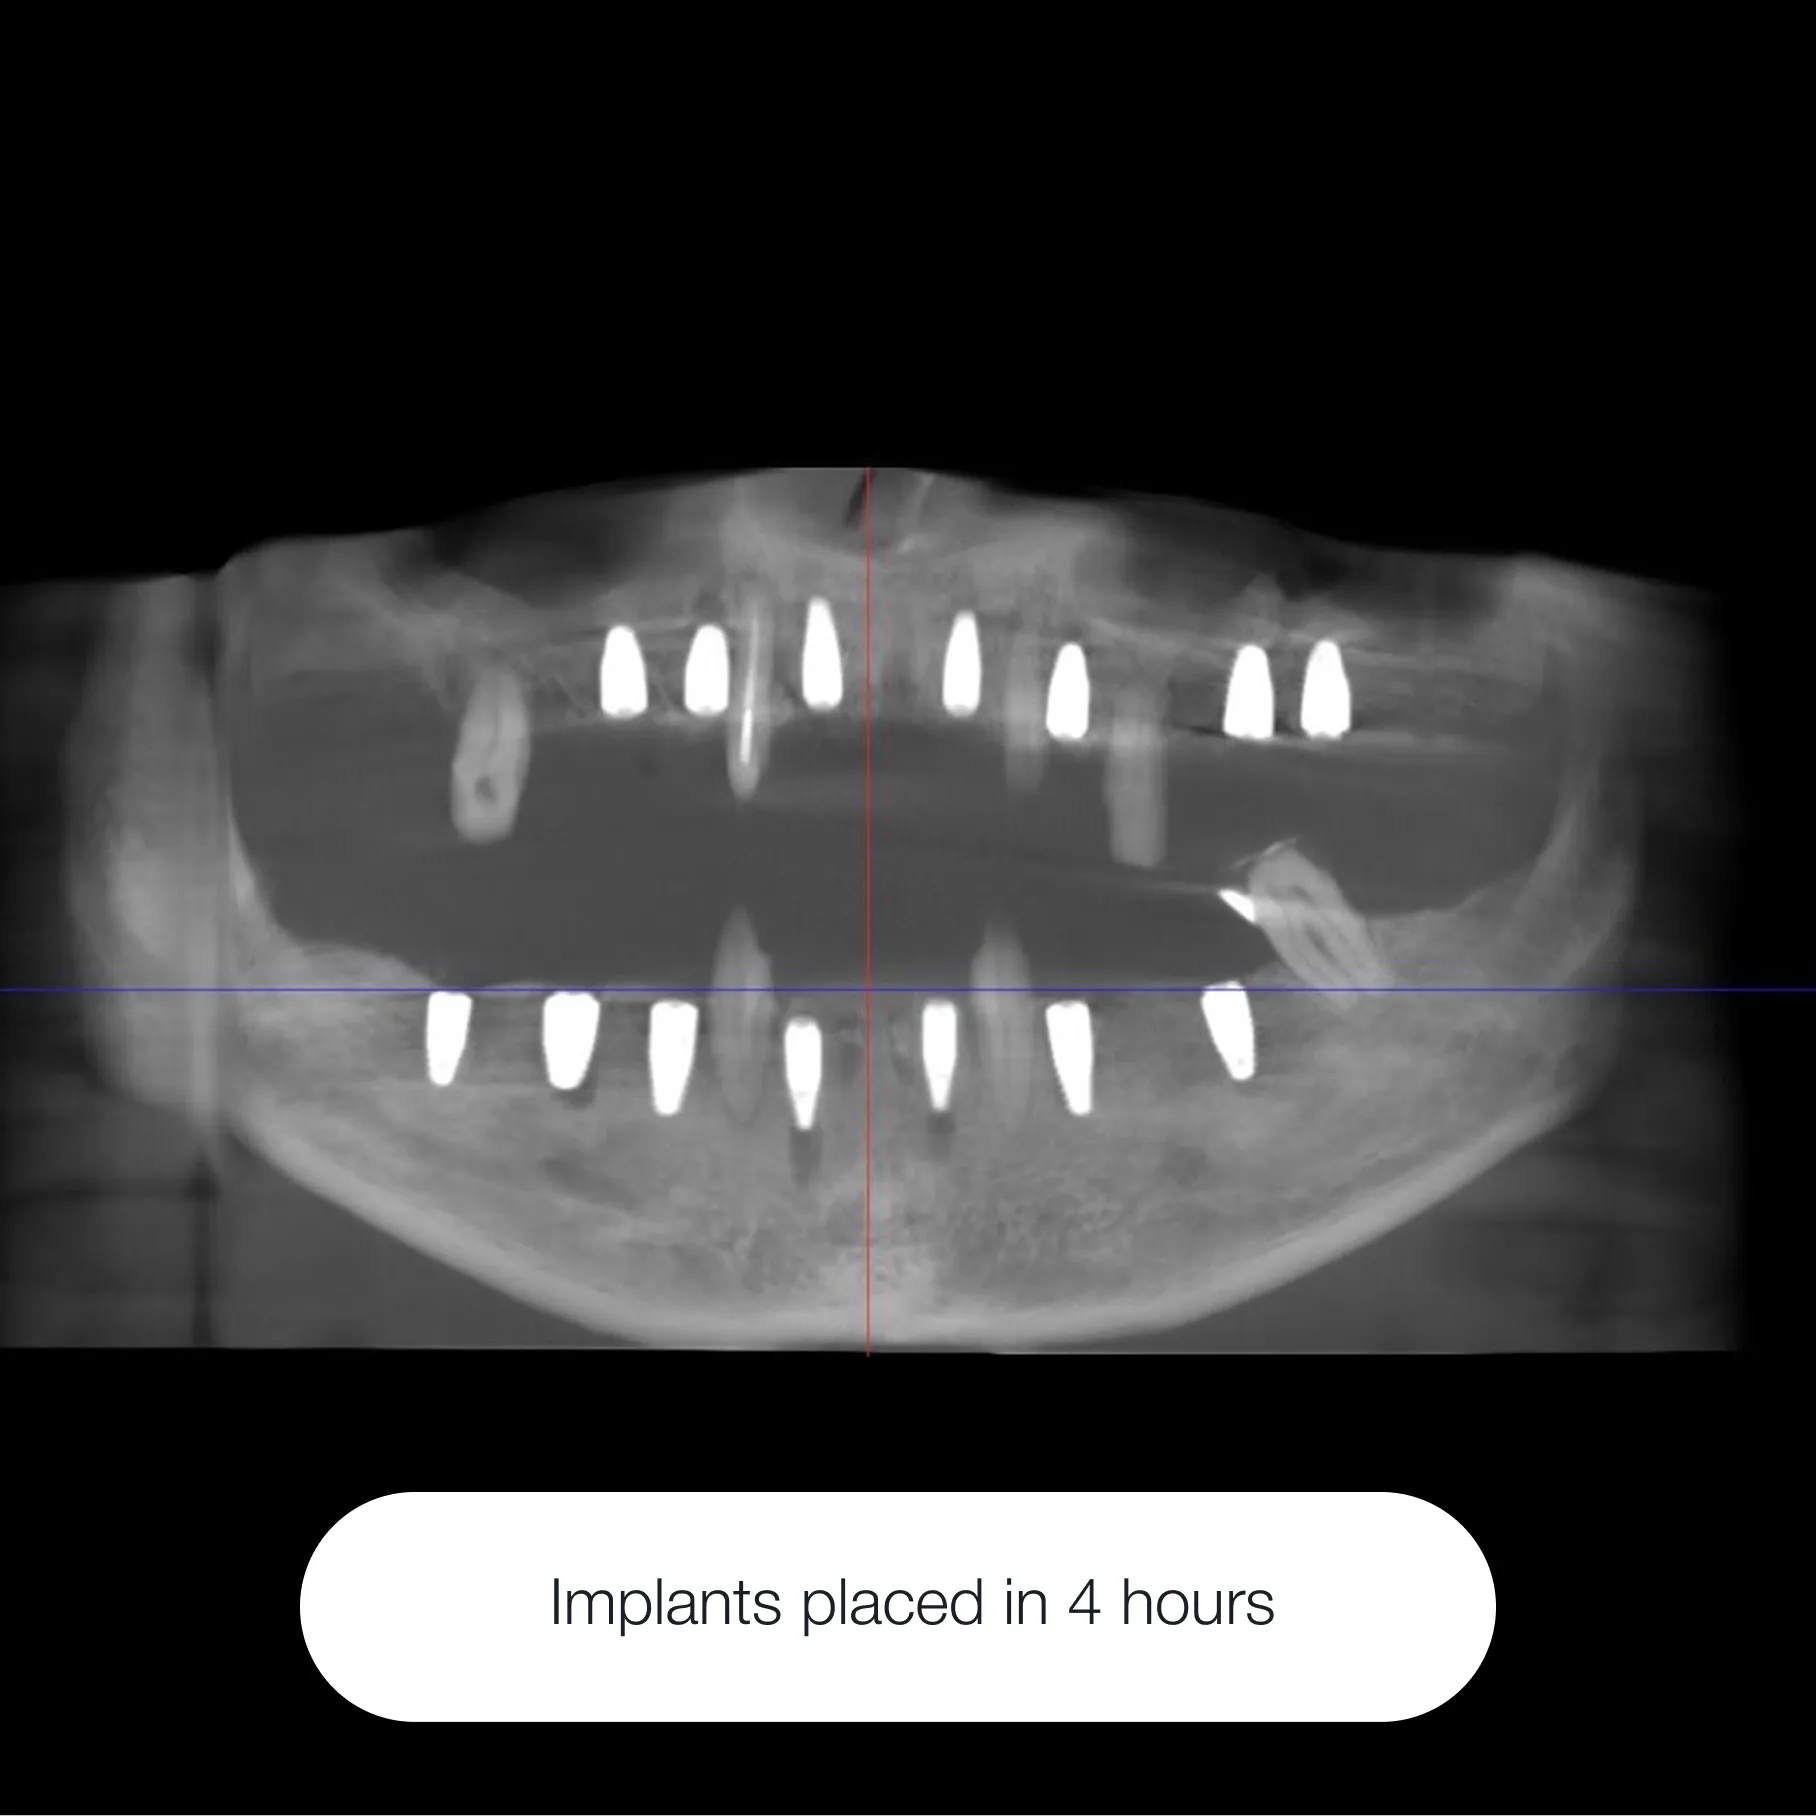

On average, it takes about 3–4 months from implant placement to the final crown.

On the day of surgery, the implant is placed and the gum tissue is sutured closed. After the healing period, the second surgical stage follows — the implant is uncovered and a healing abutment is placed to shape the gum.

Next comes the restorative phase: we take digital scans or impressions to fabricate your custom crown. At the final appointment, the permanent crown is securely placed.

This step-by-step approach ensures a predictable, long-lasting, and beautifully natural result.